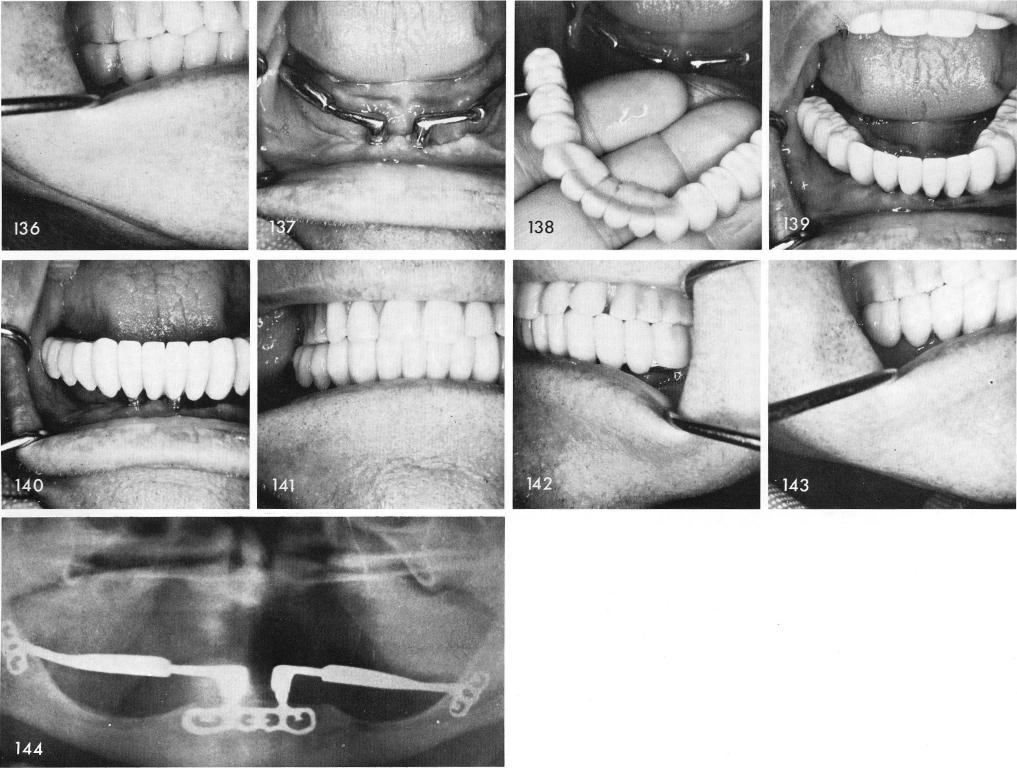

The clinical view three weeks post-operatively, fig. 137, and the processed acrylic restoration is cemented into correct position, figs. 138, 139, 140, 141, 142, 143. The post-operative x-ray, fig. 144.

1 Clinical view of symphyseal ramus system three weeks postoperatively